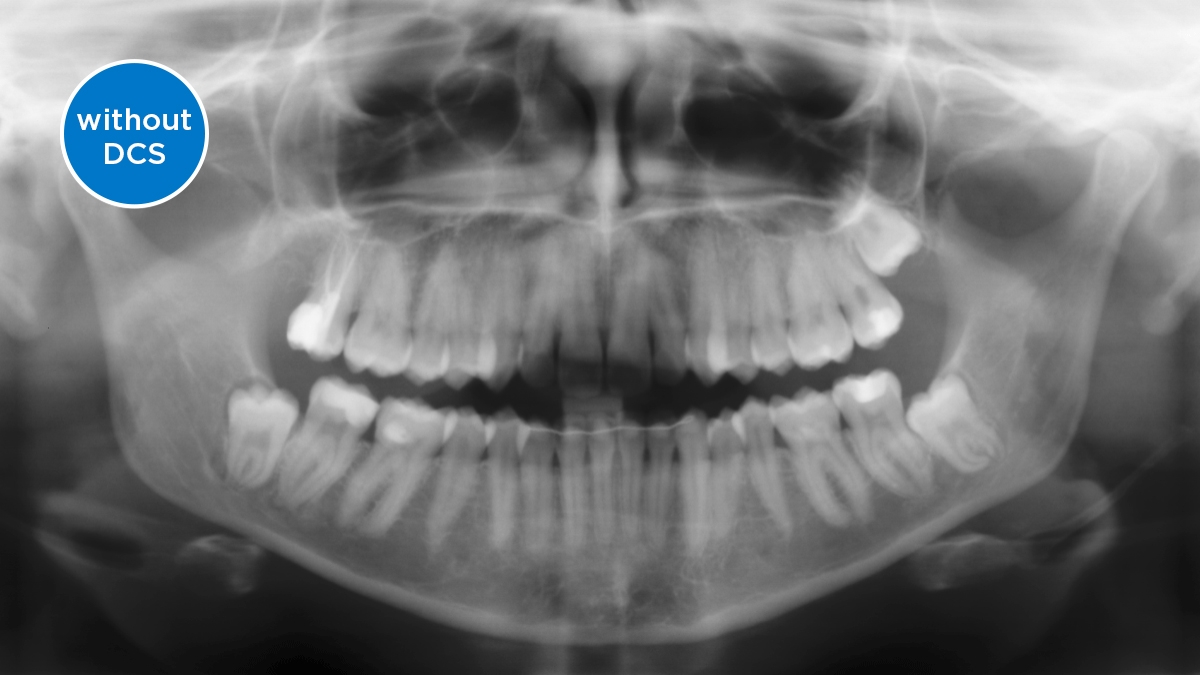

DCS converts X-rays directly into electrical signals, with no information loss. The DCS sensor creates razor-sharp, high-contrast panoramic X-ray images of exceptional quality.

Direct Conversion Sensor (DCS): Sharp Image Details

The Direct Conversion Sensor (DCS) has revolutionized the standard of panoramic imaging. X-rays are directly converted into electrical signals. Thus, there is no signal loss due to light conversion as with conventional systems. The result: images with an extremely high and high-contrast level of sharpness - even at a very low dose. For clear diagnoses and even more targeted treatment.

The image shows an X-ray image with and without DCS technology. Move the control over the image and see for yourself the difference the DCS sensor makes to the image quality.